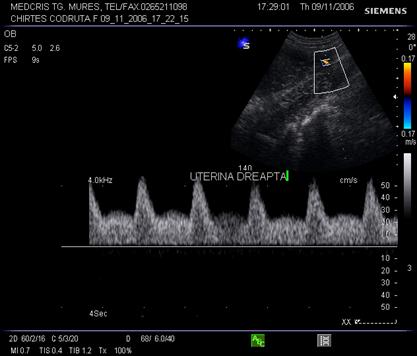

Fig. nr. 318. Doppler normal in artera uterina dupa 26 sapt.

Fig. nr. 319. Doppler cu notch prezent la 30 sapt. .Fat mic genetic pentru varsta gestationala.